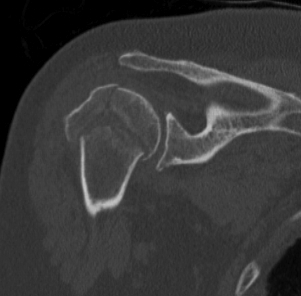

proximal humerus fracture Background ORIF with locking plate Arthroplasty Greater tuberosity fractures Lesser tuberosity fractures / avulsions Book traversal links for Proximal humerus fractures ‹ Pectoralis Major Tears Up Background ›